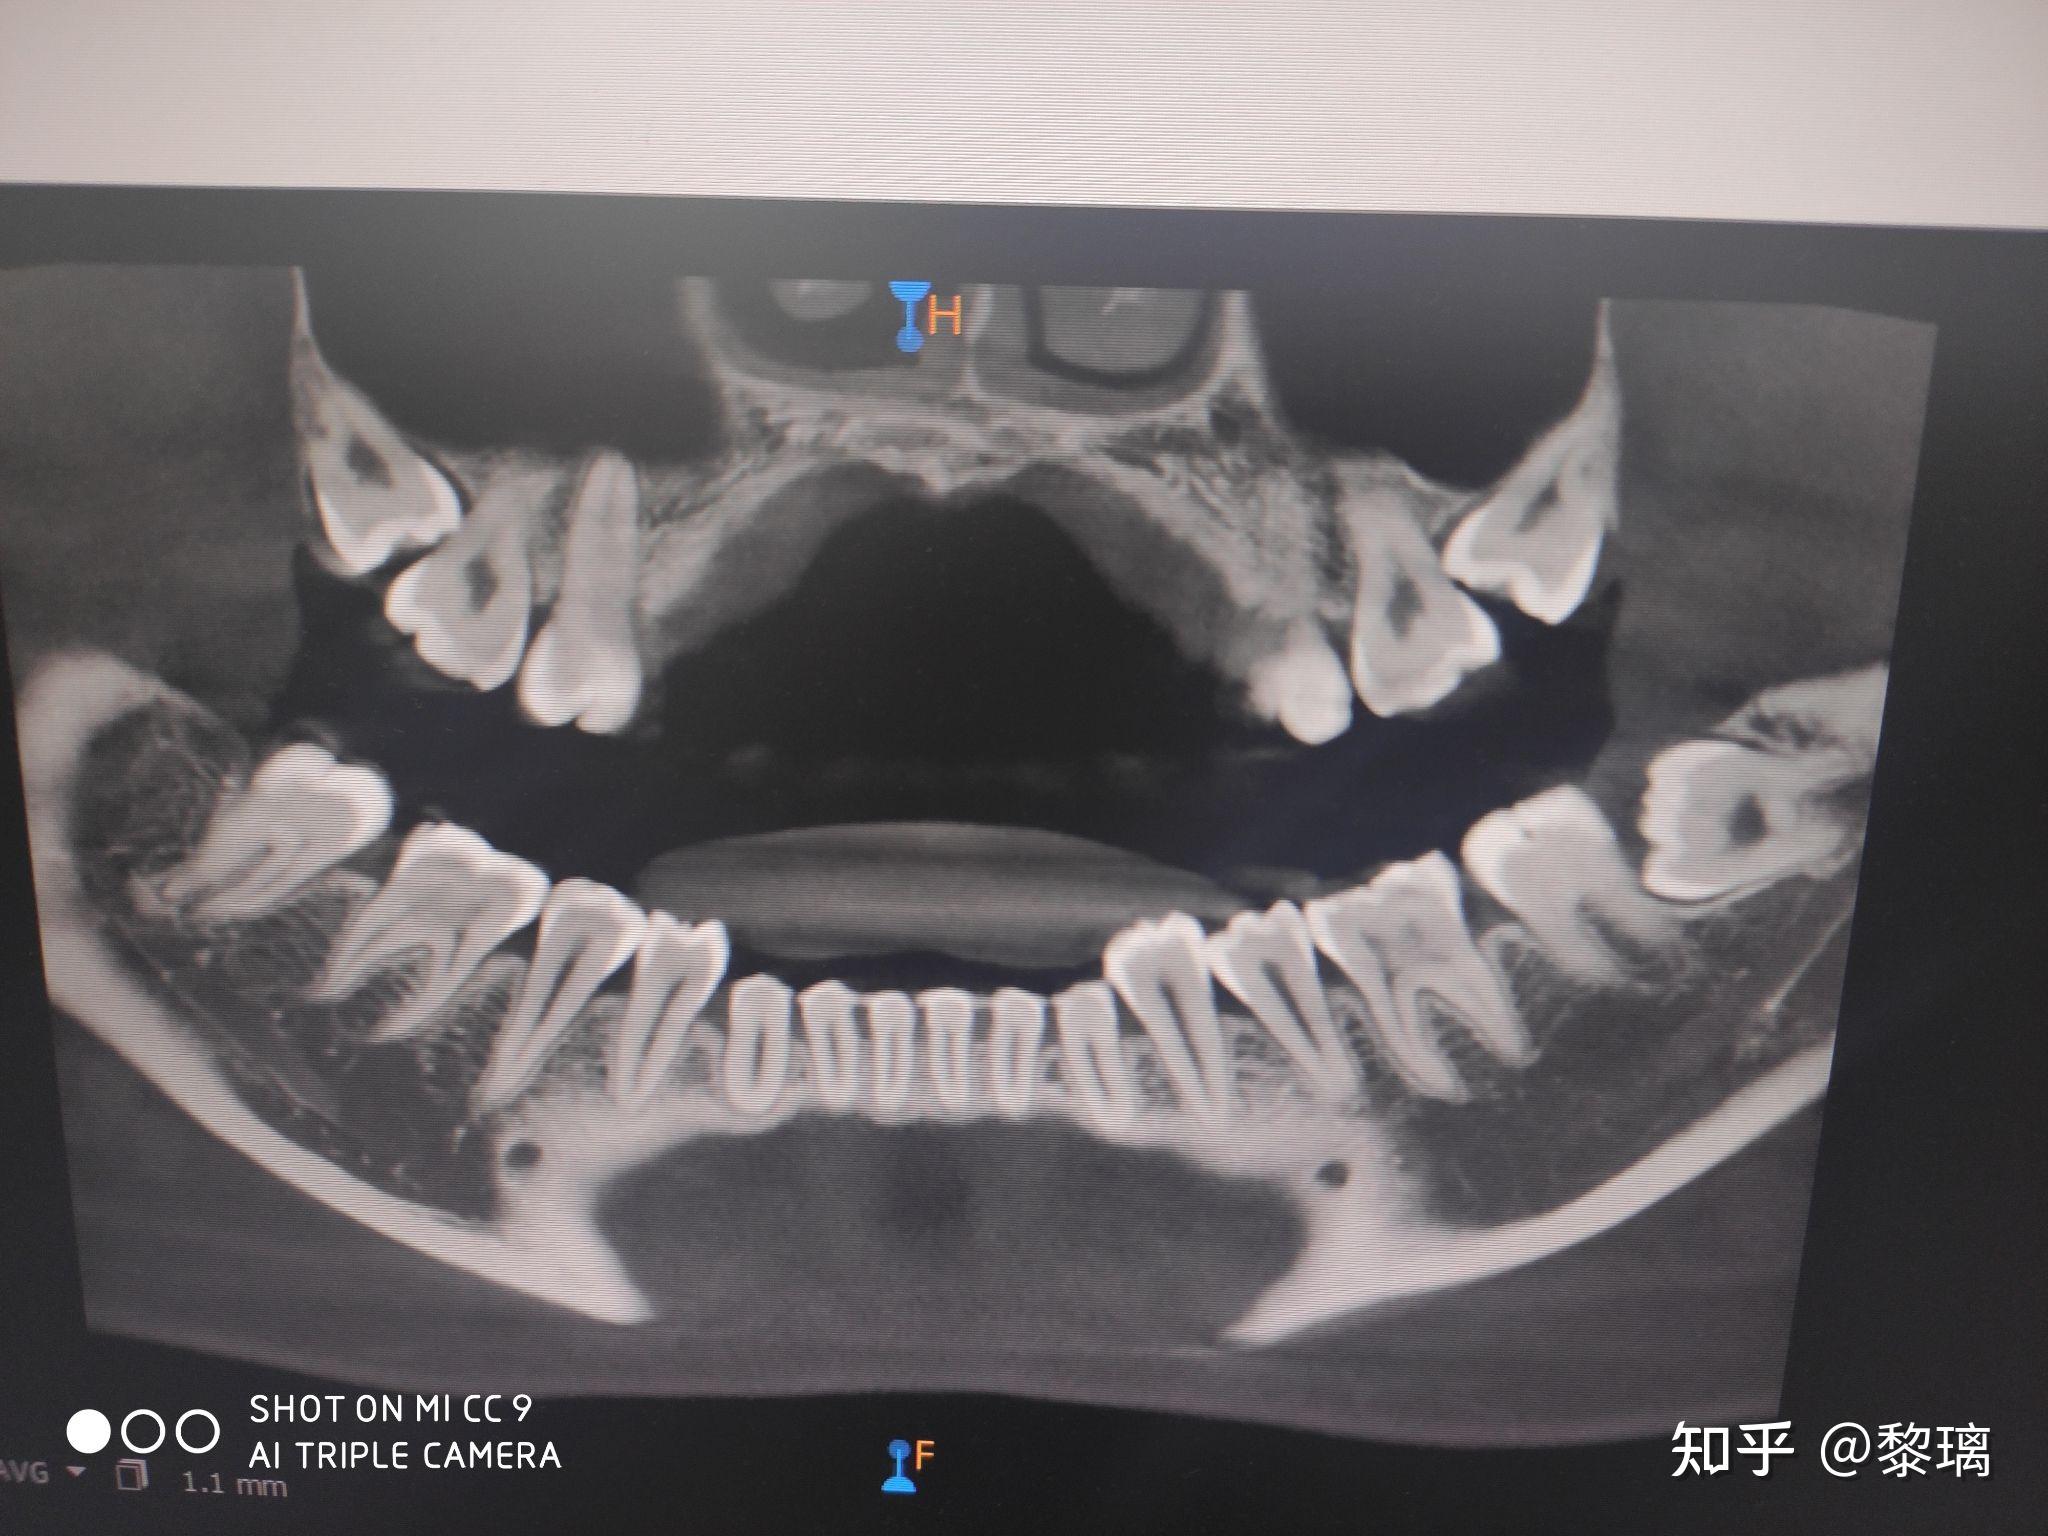

双颌埋伏阻生齿图片

图片尺寸640x500